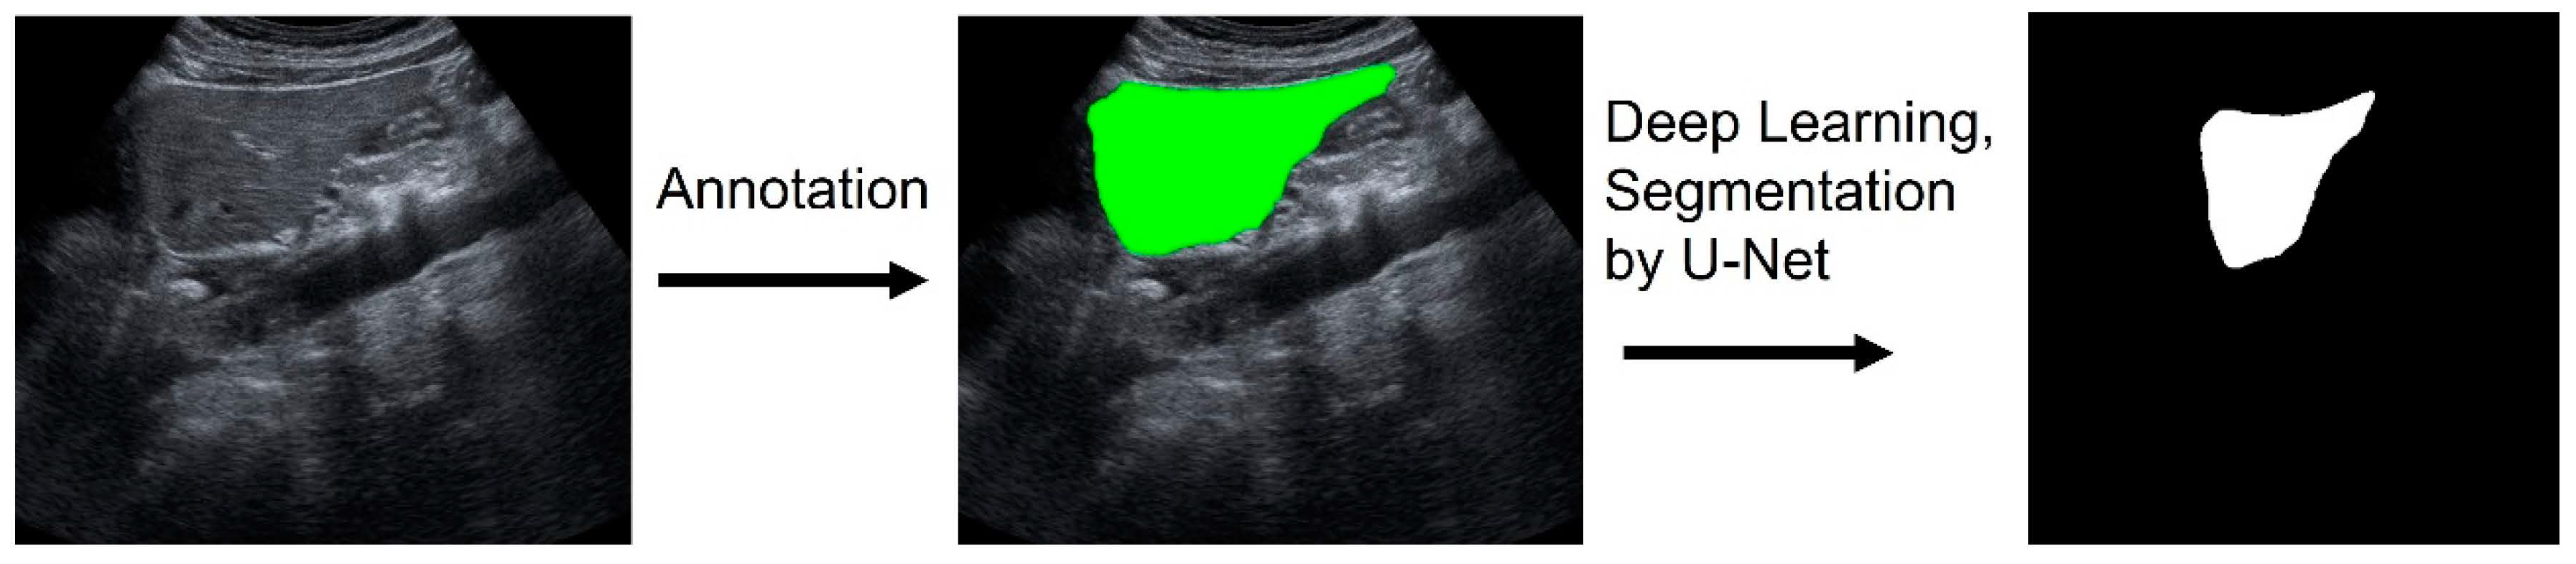

2.3. Image Pre-Processing and Machine Learning for Liver Segmentation